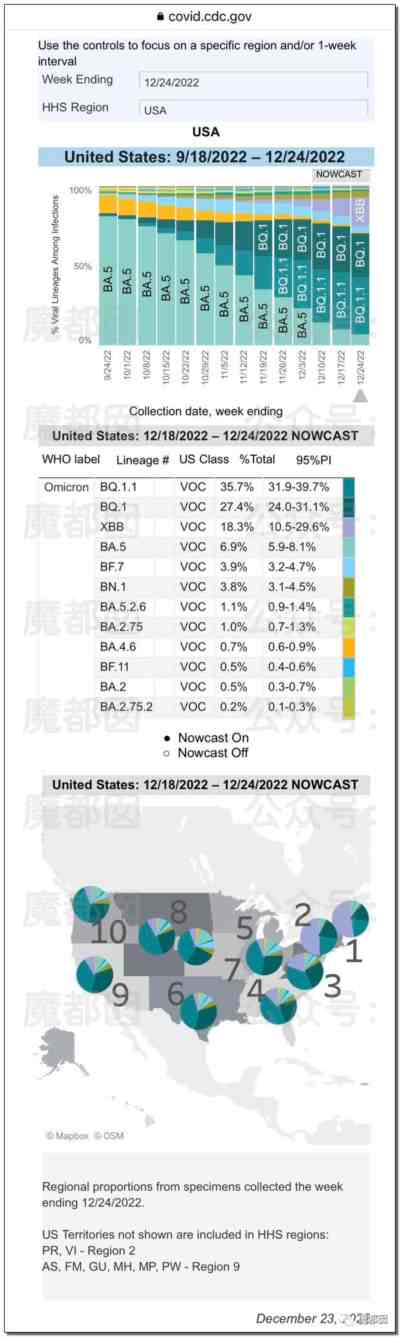

12月24日圣诞前夕,美国CDC公布了最新的新冠毒株分布图,BA.5、BF.7毒株已基本退场,BQ.1.1和BQ.1已经达峰,XBB一支崛起!

换言之,我们周围把我们搞得半死不活的毒株其实都是“老版本”,目前中国疫情爆发的主要毒株是BA.5.2和BF.7,美国的毒株变异比国内毒株要快2代。至于XBB在中国日后会有什么发展,那完全不得而知了。很有可能以后会是那种“一锅大乱炖”的情形:

因此,结论:

第一、新冠会重复感染吗?肯定会!别太指望你阳康之后的那点抵抗力,在那么多毒株面前没用。